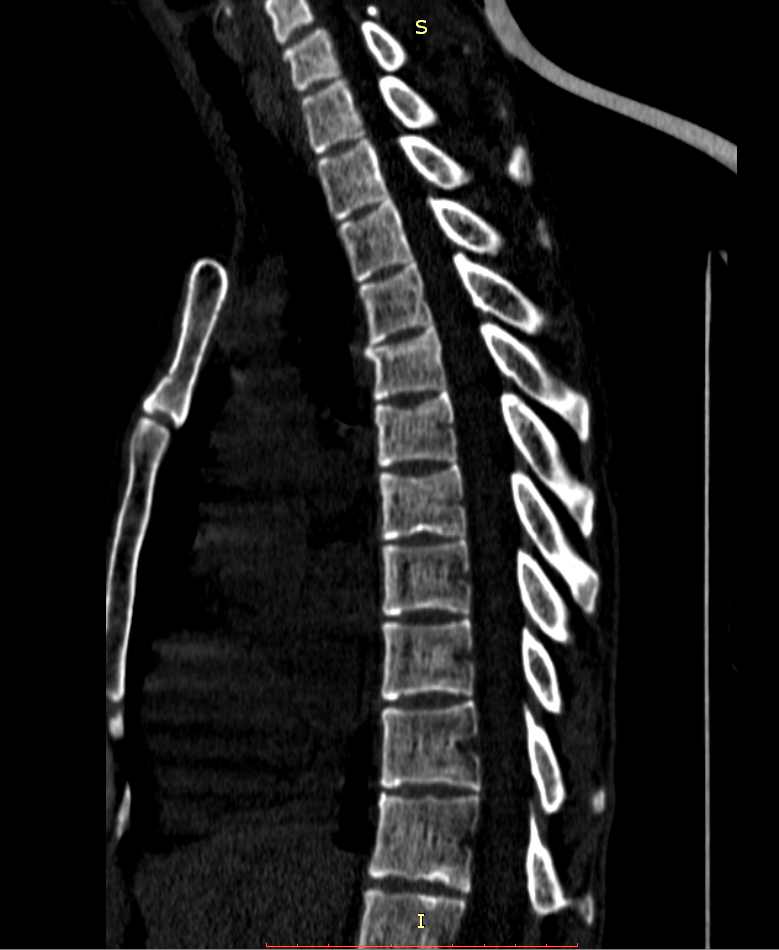

Здравствуйте! Меня сбил автомобиль. Бригада скорой помощи доставила меня в стационар с диагнозом - сотрясение мозга, ушиб грудного отдела позвоночника, компрессионный перелом грудного отдела позвоночника. При поступлении в стационар мне было сделано несколько рентгеновских снимков и поставлен диагноз - компрессионный перелом 4 грудного позвонка. Из-за "мутных" рентгеновских снимков через 9 дней мне сделали КТ и диагноз сняли на основании этого заключения.Судебная медицина - Прикрепленное изображение Мне сказали что перелом шейного позвонка у меня старый и поменяли диагноз - ушиб верхне-грудного отдела позвоночника, болевой синдром. По запросу я получила копию записи КТ. Всю запись КТ выложить не могу, т.к. не могу убрать фамилию. Выкладываю некоторые снимки: Судебная медицина - Прикрепленное изображение Судебная медицина - Прикрепленное изображение Судебная медицина - Прикрепленное изображение Судебная медицина - Прикрепленное изображение Судебная медицина - Прикрепленное изображение Судебная медицина - Прикрепленное изображение Судебная медицина - Прикрепленное изображение Действительно ли по этим снимкам можно сказать, что перелом шейного позвонка "старый"? Правильно ли описание КТ? Я не эксперт, но по-моему 5 грудной позвонок тоже поврежден. Можно ли оспорить заключение врача делавшего КТ? Если можно, то как это сделать? Ведь речь идет об установлении причинно-следственной связи между ДТП и травмой, а до ДТП у меня никаких травм позвоночника не было. Может рентгеновские снимки тоже о чем то скажут.Судебная медицина - Прикрепленное изображениеСудебная медицина - Прикрепленное изображениеСудебная медицина - Прикрепленное изображение

Для этого надо исследовать все сканы. Желательно - с 3D-реформацией изображения. С внимательным анализом костной структуры на уровне дефекта (есть ли признаки отека костной ткани в его зоне, наличие реакции мягких тканей, состояние краев фрагментов и т.д.). Получите все сканы КТ на диске или на флешке (они должны храниться в архиве КТ). И проконсультируйте их у высококвалифицированного специалиста по КТ и/или в любом крупном Бюро судебно-медицинской экспертизе, в штате которого есть эксперт-рентгенолог. Возможно, понадобится сделать контрольное КТ исследование с целью обнаружения динамики выявленных изменений (впрочем, вопрос об этом будет решен после ознакомления рентгенолога с КТ, т.к., возможно, доп.исследование не будет необходимо или же более целесообразным окажется иной вариант лучевой диагностики). По результатам консультации станет понятно, есть ли реальные основания для заявления мотивированного ходатайства о назначении дополнительной или повторной экспертизы (как это сделать - подскажет Ваш адвокат).